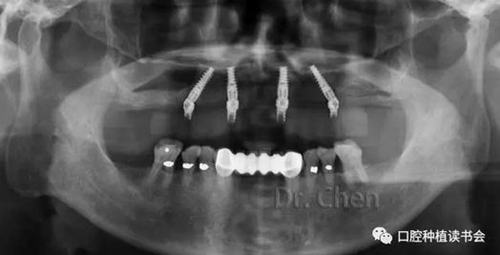

必要時用記號筆標注便于技師調(diào)改(圖7),必要時拍攝曲面斷層片(圖8),可見所有基臺臨時套筒完全就位。

8.jpg

▲ 試戴樹脂牙就位后拍攝曲斷片

曲斷片顯示所有氧化鋯接口與Multi-unit基臺之間完全就位,骨水平穩(wěn)定于植體頸部(圖13)。